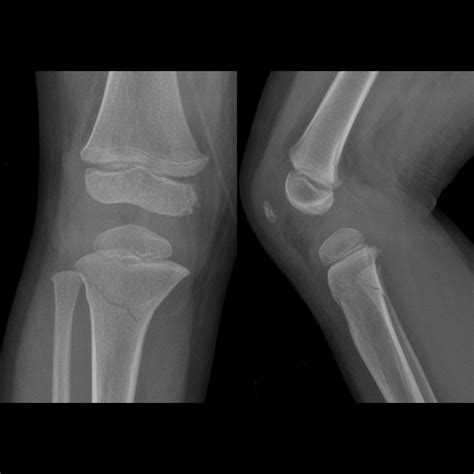

Pediatric Mallet Finger Fracture | Pediatric Radiology Reference ...